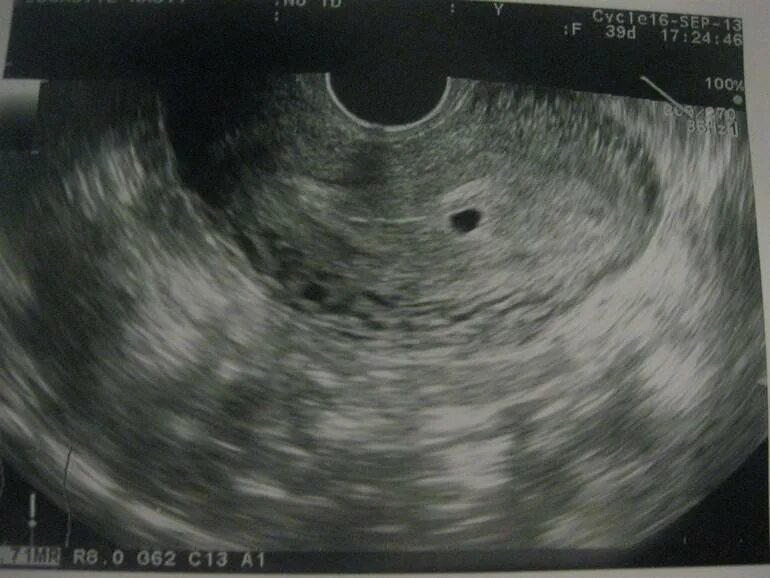

Как называется узи на ранних сроках